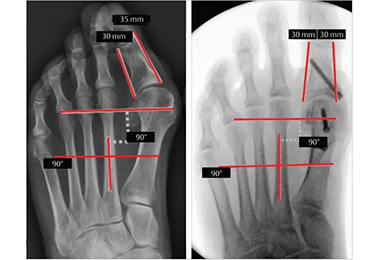

• Chirurgie mini-invasive de l'hallux valgus

L'hallux valgus est une déformation osseuse à la base du gros orteil, caractérisée par une déviation latérale de l'orteil et une saillie douloureuse de l'articulation métatarsophalangienne (MTP). Bien que des traitements non chirurgicaux comme des orthèses ou des modifications de chaussures puissent atténuer les symptômes, la chirurgie est souvent recommandée pour En savoir plus